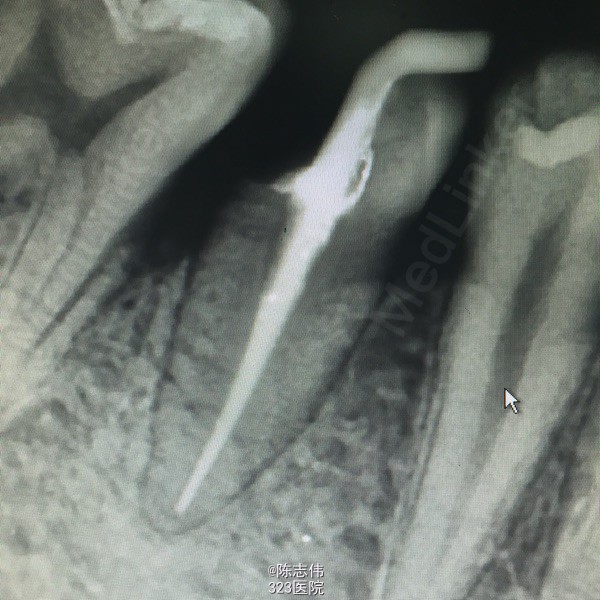

17,45RCT+桩+冠

处理:局麻下16,17,45去龋,16龋净未露髓,清理干燥隔湿后垫底+3M树脂充填。17,45揭开髓室顶,丁香油棉开放,降颌

- 王凌回复美雅:根管很漂亮

- 美雅回复张景元:谢谢分享,45是不是稍微有点欠充呢?而试尖片看起来是不是有点超啊

- 张景元回复宋伟颉:谢谢分享这么完整的病例!根管治疗做得很漂亮,讲解也很到位,个人觉得根管之后还是需要进行冠修复,才能保证咬合功能不受太多影响!

根管做的好漂亮啊,佩服啊!